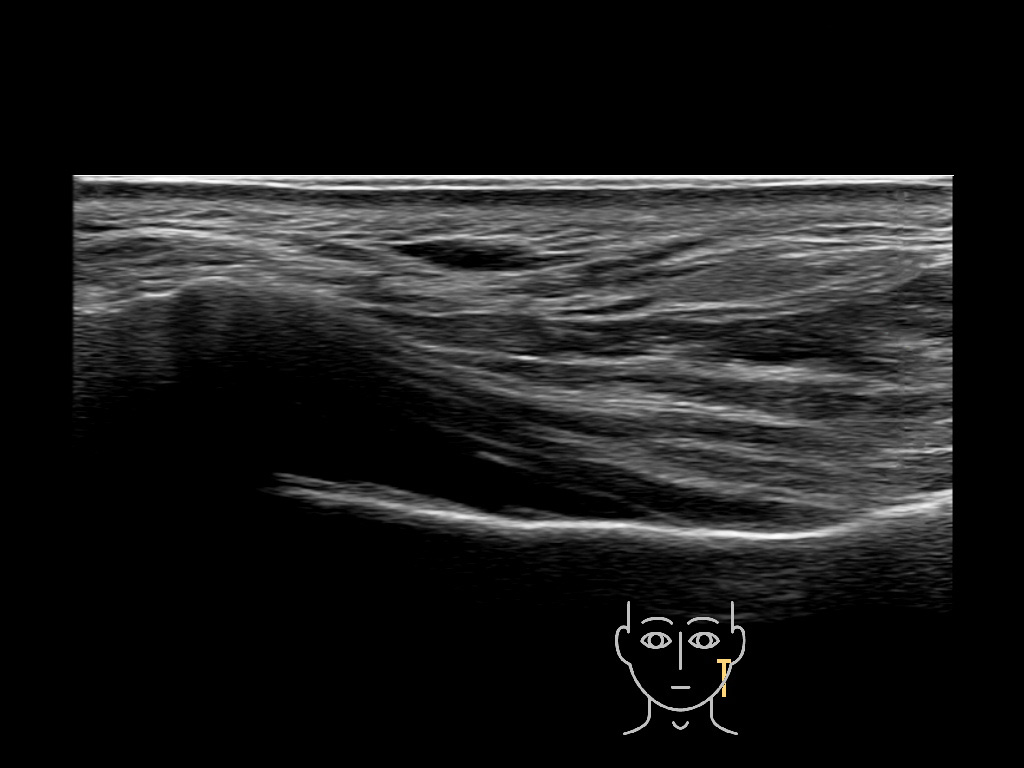

Filler deposits may end up unintentionally in the SMAS or fascial layers of the skin. Very often this will not lead to adverse events, however, adverse events ( nodules, migration / redistribution impaired muscle movement and smiling and malar edema) are are often related to filler ending up in the SMAS or fascia.

Study the first image to recognize the different layers. If you are sure about the layers, swipe to the second image to view the answer (if applicable).